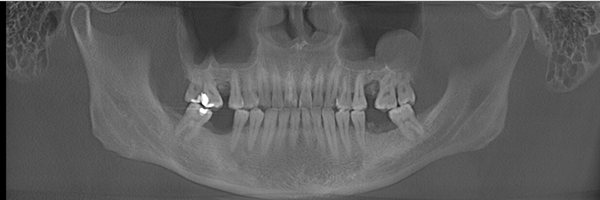

王先生术前牙齿全景片